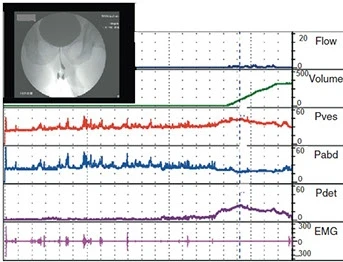

O estudo urodinâmico consiste em observar o armazenamento, transporte e esvaziamento de urina da bexiga. Além de fazer diagnósticos, atuar na prevenção de doenças e prescrever medicamentos, o profissional desta área pode realizar cirurgias no trato urinário de homens e mulheres e nos órgãos genitais masculinos.